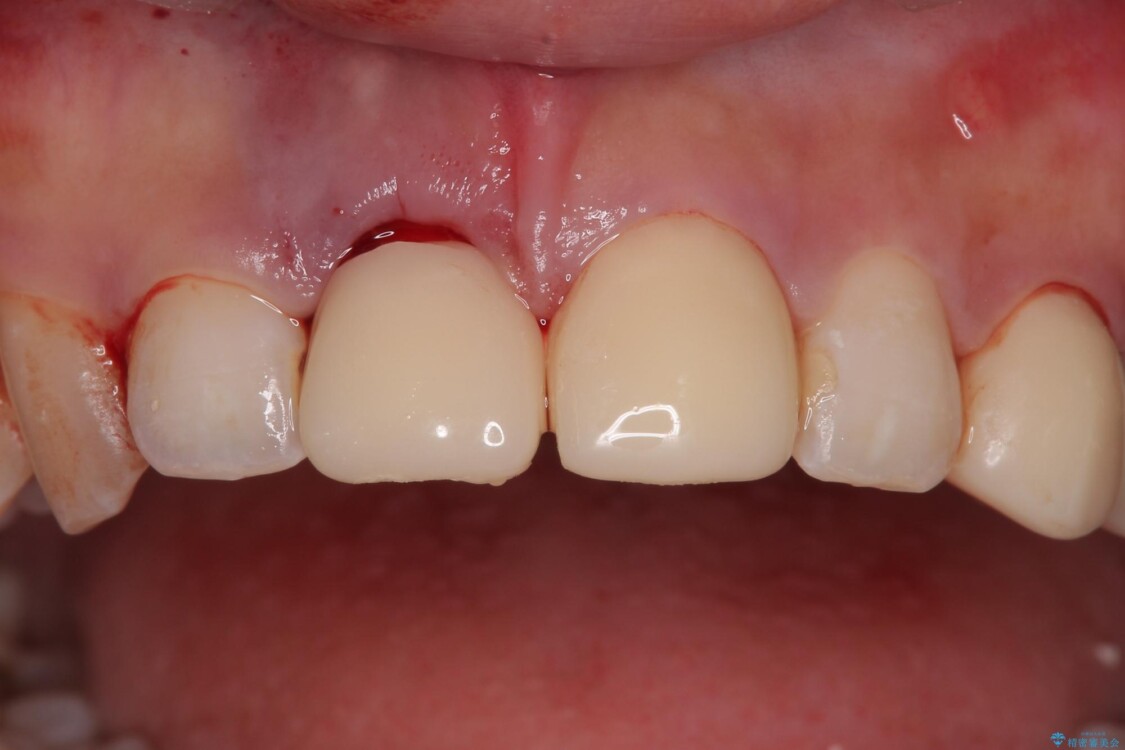

治療途中

• 「抜歯してブリッジ」と言われた20代女性が選んだ治療とは|たった4か月で自然な笑顔に抜歯即時インプラント+審美補綴の症例 治療途中画像

▶右上中切歯

抜歯後、即時インプラント埋入

審美性を考慮し、仮歯を即日装着

治療期間を最小限に抑えつつ、自然な前歯のラインと歯ぐきの形を維持